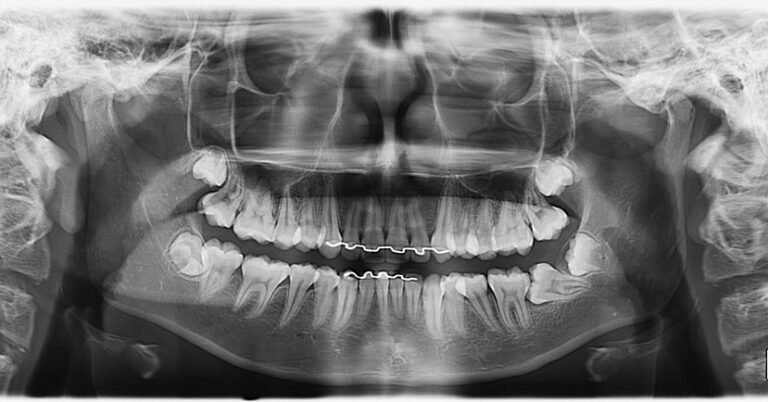

A Patologia Oral e Maxilofacial é a especialidade responsável pelo diagnóstico e tratamento de doenças que afetam a boca, mandíbula e estruturas faciais. Atua na identificação de lesões, cistos e tumores, garantindo diagnóstico preciso e tratamento adequado para preservar a saúde bucal e geral do paciente.